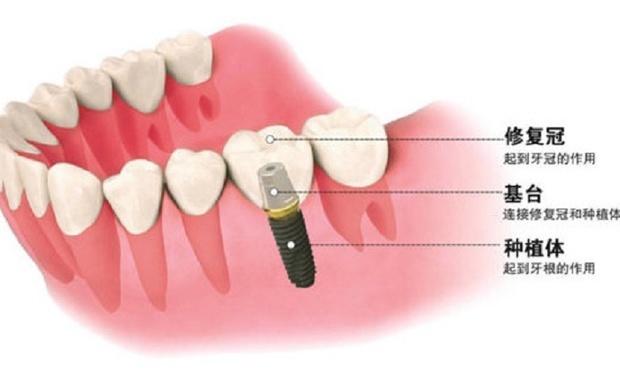

3. 植入種植體:這個(gè)時(shí)候開始進(jìn)行第一期手術(shù),手術(shù)將在牙槽骨上選擇合適的位置打洞,植入種植體后縫合創(chuàng)口,正常情況下整場(chǎng)手術(shù)時(shí)長在半個(gè)小時(shí)左右。

5. 等待骨愈合:種植體植入牙槽骨后需要一個(gè)相互適應(yīng)的過程,在這個(gè)過程里種植體會(huì)逐步的與骨組織結(jié)合,根據(jù)受力和其他影響因素,骨結(jié)合所需的時(shí)間也是因人而異,大概在3-6個(gè)月左右。

6. 安裝基臺(tái):骨愈合后就可以進(jìn)行二期手術(shù)使種植體穿出牙齦,為了幫助牙齦軟組織更快的愈合,會(huì)通過手術(shù)把種植體的覆蓋螺釘取替換成愈合螺釘。

7. 覆蓋義齒:兩至三周待軟組織成型后,就可以把愈合基臺(tái)換成基臺(tái)佩戴種植牙冠了;至此種植牙全部流程都已全部完成。